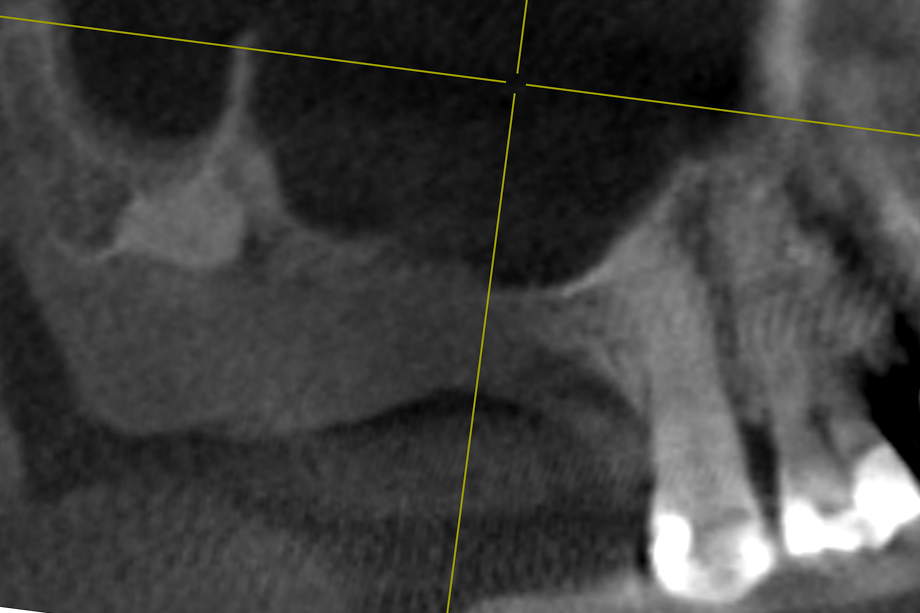

01/14 - DVT control after sinusitis surgery, residual bone height 1 mm

Two-stage sinus lift with maxresorb® & collprotect® - Dr. S. Kistler

02/14 - Transversal section to determine depths of the sinus floor